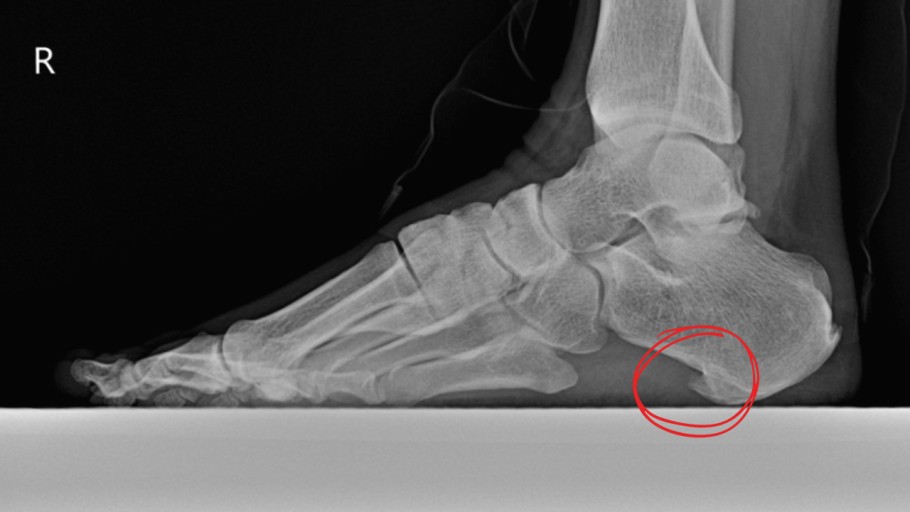

8. 발바닥에 딱딱한 결절

일부 환자들은 발꿈치에 결절이 생길 수 있습니다. 결절은 발꿈치 뼈에 작은 돌출부위로, 족저 근막염이 장기화되면 나타날 수 있습니다. 이 결절은 발꿈치를 눌렀을 때 통증을 유발합니다.